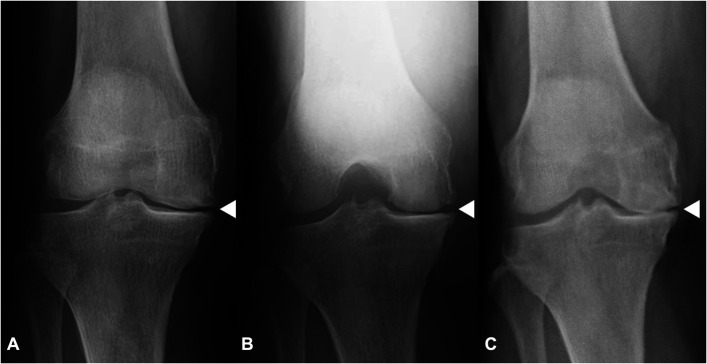

Results: LEA-Gait showed greater lateral inclination of the tibia and TJLA compared with standing, which resulted in increased varus HKA (all p < 0.01). No significant differences were observed in femoral or tibial rotation. Greater ΔTMA (tibial mechanical axis) and ΔTJLA were observed in knees with milder malalignment in standing. Medial joint space appeared open in 13 knees on standing and 5 on Rosenberg views but was closed in all 40 knees during gait.

Conclusions: LEA-Gait differed significantly from LEA-Standing, revealing medial joint space closure and alignment abnormalities not captured by static evaluations including standing radiographs and Rosenberg views. These findings highlight the importance of considering the possibility of cartilage wear that may not be apparent on static radiographs.